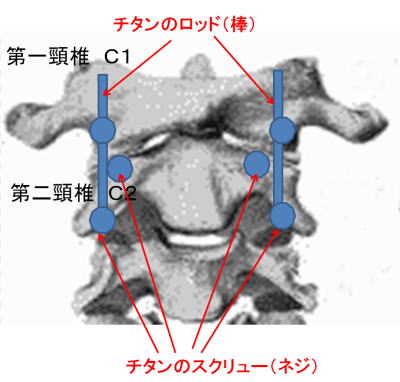

手術では、切開後、下の図にあるような第二頸椎を取り巻く筋肉や脊椎、末梢神経、動静脈などどへの損傷、影響を最低限に腰から採った骨を第一頸椎と第二頸椎の間に挟みつつ、4本のチタンスクリューと2本のチタンロッドで幹部を固定する。スクリューをうつ場所はドリルで穴を開けるという。 ◆手術の内容とInformed Consent 入院して一週間後、私は大手術を受けることになる。 手術の内容だが、折れて陥没した第二頸椎を自分の腰からとった骨を挟んで第一頸椎にチタン合金で構造化し固定化するもので、チタンのスクリューやロッドを6本使っている。まだ3次元画像はもらっていないが、後に術後のレントゲン写真を見せられた。これについても入手次第、掲載したい。 下は手術前夜に執刀医が私と妻との間で行われた Informed Choice and Consent時に示した手術の物理的な概念図である。構造設計図といってもよい。これは個室の前にあるカンファレンス室で執刀医、青山、妻の3人で1時間ほどかけ行われた。

そして翌日の11月19日午後から夜に及ぶ手術では、妻が個室(病室)に待機し、万一インフォームドコンセントの内容からはずれて麻酔、手術などをする場合、すぐに執刀医から妻に連絡が行くとされた。 手術では、当初通りに行われたこともあり、待機する妻への連絡は終了時までなかった。 ◆手術の具体的内容 C1が第一頸椎、C2が第二頸椎であり、上の図が側面図、下の図が組の後ろから見た側面図である。スクリュー4本、ロッド2本は素材がチタン合金であい、櫓を組んで第一、第二頸椎を腰から取った自分の骨を挟んで固定する。  主治医がInformed Consentで示した青山貞一手術の概念図(1) 慈恵医科大付属病院脳神経外科 2010.11.18 下は青山が上図を元にのちに作成したもの。ただし、下図は第二頸椎骨折、陥没後ではなく、健康な頸椎上にチタンのスクリューやロッドを書き加えている。さらに3次元で立体的に可視化しないとその構造は理解されにくい。  青山貞一による手術の概念図 下は使用するチタンスクリューのイメージである。   出典:http://www.sophiatech.co.jp/implans/screw_image/screw_image.html 手術ではたとえば以下のようにして使うことになる。ただし、以下はイメージ図。   それぞれの位置 背面図 出典:http://www.orihime.ne.jp/~one-/tekious.htm 手術の前々日、前日と2回に渡り麻酔専門医から何度も説明を受けた。麻酔の手順、心得などについても説明を受けた。 大手術は慈恵医科大学付属病院の脳神経外科、麻酔科などの専門医師5名による特別グループ構成で11月19日午後から夜にかけ行われた。 12時過ぎ、中央棟16階にある私の個室から看護師により車椅子で16階からエレベータを使って3階の手術に向かった。手術室到着後、麻酔専門医により点滴形式で全身麻酔が行われた。覚えているのはここまでである。 その後7-8時間はまったく記憶はなく夢も見ていない。 手術後すぐに、5階にある集中治療室(ICU)に移された。 ICUでは主動脈(Aライン)、静脈、末梢系はじめ各所に10本以上のチューブが体に差し込まれており、またオシッコなどの排出系もすべてチューブとなっていて身動きできなかった。入院後、一番きつかったのはこのときである。 慈恵医大病院中央棟のICUはかなりの数あり、手術を受ける患者には希望すると手術の前日までにICUを見学することができる。私は希望し前日にしっかり見学しICU側から説明も受けた。 肝腎な手術の内容は、上述のように落下転倒で折れ陥没した第二頸椎と第一頸椎の間に、腰から取った骨を挟み約2mm直径のチタン(金属)2本とそれにブリッジをかけるように固定することでした。チタンの棒は計4本使用している。 上記の手術内容についても、外来検査時から手術の前日まで、あらかじめ模型とグラフィックスをもとに主治医に何度も説明をしてもらった。 手術内容と方法には、当然のこととして代替案が多数ある。そのかかから医師と議論しながらひとつを選ぶことになった。代替案によりプラス、マイナス、リスク、費用が変わる。 また、もし手術で実際に首を開いたところ、第一案が難しい場合は第二案、第三案と次善の策についても優先順位を付けることになった。この説明と質疑にはかなりの時間が費やされた。この辺はInformed Consentの主要部分となる。 本来、第一頸椎と第二頸椎はそれぞれ独立して動くことで、人間は誰でも首が自由に回るのだが、第一と第二を固定化したので、手術によって直っても仰角、回転角ともに制限がある。リハビリなどにより健康な方の70%程度まで戻るかも知れないと言われた。 上述のように、私自身、3週間に及ぶ入院の中では、ICUから個室に移った20日が一番きつかった。翌日は一日安静にしていた。実のところ私が入院中に安静にしていたのは、この日(20日)くらいかも知れない。 19日夜から点滴が開始されていたが、20日の夕方から食事がだされた。食事と並行してブドウ糖などの点滴を行い栄養を体に送り込んだ。点滴にはブドウ糖とともに手術時の各種傷口に対応するための抗生剤が含まれる。 22日以降、手術に関連した痛みがかなり減ってきた。術後、一切の鎮痛剤を使っておらず看護師さんらはびっくりしている。痛みは人によって個人差があるようだ! ところで今回は、11日に東京都品川区にある旗の台脳神経外科に診察にでかけたときから、現在に至るまで徹底的にInformed choice and consentを心がけ、すべてに渡り主治医(脳神経外科執刀医、呼吸器主任、糖尿など生活習慣病関連の主任、麻酔主任)らからの説明を受け、その都度理解、認識した上で判断した。 たとえば呼吸機能を回復させようとすると血糖値やLDLが上昇するなど新たな問題が起こるが、それらを承知の上で何を優先するかが術前の大きなポイントとなる。これについても、私のここ数年の経験を伝えた。 医者側も驚いていたが、やはり患者や家族は医者任せ、看護師まかせではなく、主体性を持って対応することの大切さを実感している。 下は健康な人の第一頸椎(上)と第二頸椎(下)の側面図である。 第一頸椎 出典:http://video.about.com/backandneck/Cervical-Spine-Anatomy.htm 第二頸椎 出典:http://video.about.com/backandneck/Cervical-Spine-Anatomy.htm 下のレントゲン写真は術後に撮影したものである。 退院後初の検査時に主治医より提供を受けた。第一頸椎と第二頸椎の間に腰骨を挟み、チタン合金で第一頸椎(長いスクリュー)、第二頸椎(短いスクリュー)で固定している様子が3次元の立体図で良く分かる。  手術後の頸椎レントゲン写真(2010/12/13) 出典:東京慈恵会医科大学付属病院脳神経外科 以下は、CT及びMRIで見た手術個所の断層図である。退院時、希望していたCT及びMRI断層画像データをCD媒体で提供された。画像は専用ソフトだけでなくWindowsXP,7などのブラウザでも見れる。  出典:東京慈恵会医科大学付属病院脳神経外科 下はCT画像に見る第二頸椎に入れたチタンスクリュー(ネジ)。断層撮影なので部部しか見れない。  CT断層画像に見る青山貞一の手術後(2010年11月20日撮影)。 慈恵医大付属病院 下もCT画像に見る第二頸椎に入れたチタンスクリュー(ネジ)。断層撮影なので部部しか見れない。チタンスクリューは4本、チタンロッド(棒)は2本入れてある。  CT断層画像に見る青山貞一の手術後(2010年11月20日撮影)。 出典:慈恵医大付属病院脳神経外科  CT断層画像に見る青山貞一の手術後(2010年11月20日撮影)。 出典:慈恵医大付属病院脳神経外科  CT断層画像に見る青山貞一の手術後(2010年11月20日撮影)。 出典:慈恵医大付属病院脳神経外科  CT断層画像に見る青山貞一の手術後(2010年11月20日撮影)。 出典:慈恵医大付属病院脳神経外科  CT断層画像に見る青山貞一の手術後(2010年11月20日撮影)。 出典:慈恵医大付属病院脳神経外科 下は腰の骨の採取場所を示している。また手術時の切開位置を示している。首の裏を縦に12cmほど切開している。  主治医ががInformed Consentで示した青山貞一手術の概要図(2) 慈恵医科大付属病院脳神経外科 2010.11.18  頸椎を取り巻き上下に縦断する筋肉 出典:http://video.about.com/backandneck/Cervical-Spine-Anatomy.htm  頸椎と隣り合わせに上下に縦断する脊髄 出典:http://video.about.com/backandneck/Cervical-Spine-Anatomy.htm 万一動脈を切った場合は、すぐに輸血を開始するという。  頸椎と隣り合わせに上下に縦断する動脈 出典:http://video.about.com/backandneck/Cervical-Spine-Anatomy.htm 下は慈恵医大付属病院のCTで撮影した青山貞一の頸椎と隣り合わせに上下に縦断する動脈である。  CT断層画像に見る青山貞一の頸椎と隣り合わせに上下に縦断する動脈(撮影2010年11月17日)。 出典:慈恵医大付属病院脳神経外科 英国医学会で頸椎手術に関連し想定しているリスク(合併症を含む)を以下に示す。すなわち外科手術により物理的に幹部を固定化したとしても、将来、以下のようなリスクがないわけではないようだ。  出典:http://video.about.com/backandneck/Complications-of-Spinal-Surger.htm ◆全身麻酔による大手術 入院から一週間後の11月19日午後、全身麻酔後に大手術をすることになった。慈恵医科大学付属病院の中央棟3階にある手術室で手術を受ける。 手術の数日前から麻酔の専門医2名から説明を受ける。また看護師から手術当日の実務手順について資料をもとに説明を受ける。 お昼に病室がある16階から専用エレベータで手術室がある3階に直行し、その後、麻酔との対話の中で点滴により全身麻酔がおこなわれ、5名のチームによる手術が開始された。 慈恵医大脳神経外科の手術では全国でここだけ、手術中にCT断層撮影が可能とのことである。 午後8時過ぎ手術は終了し、5階の集中治療室(ICU)に移された。麻酔が切れた後、妻や池田さんと会話を交わした。大手術は大成功であった! 現在の麻酔技術の進歩はすさまじく、5分単位で全身麻酔をオンオフできるという。医師は麻酔技術は日進月歩で進歩しており、すばらしく切れがよいと言っていた。  慈恵医大病院中央棟3階にある手術室のイメージ 3階、4階が手術室。5階が集中治療室(ICU)、6階より上が病棟 出典:慈恵医大病院公式Web  集中治療室(ICU)の一部(イメージ) 出典:慈恵医大病院公式Web このように11月19日午後から夜に行われた手術では、当初予定の内容を関連する神経系、動脈系などに損傷を与えることなく実施できた。 ★手術成功のお知らせ(池田こみち) 術後の痛みだが、鎮痛剤を注射してもらうほどの耐えられない痛みは退院までなく、当初からあった後頭(こうとう)神経痛も次第に弱くなってきた。それ以外の痛みとしては、寝る角度により腰から骨を採った場所がちくりと痛むことがル程度である。 以下は青山貞一の手術を担当してくれた大橋医師のプロフィールです。